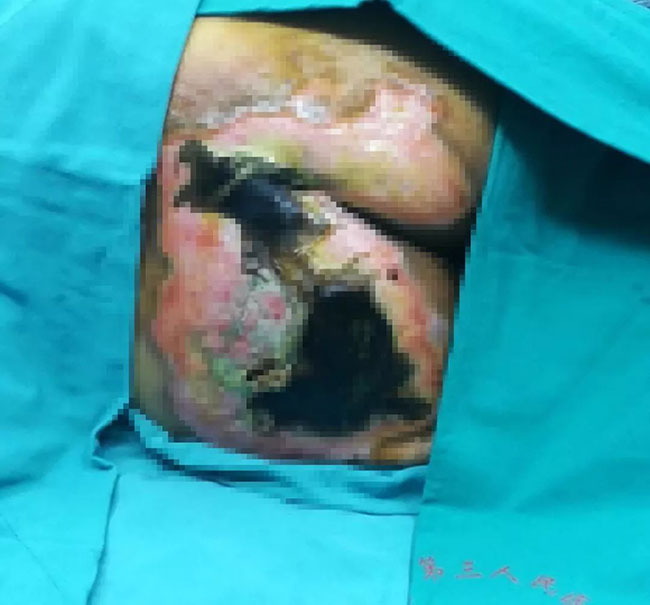

2017年12月1日,患者被送到廣西江濱醫(yī)院普通外科,經(jīng)診治,為燙傷后導(dǎo)致的壓瘡,創(chuàng)面淤黑、壞死,面積為17cm×17cm。

在對創(chuàng)面進行消炎處理后,2017年12月5日,廣西江濱醫(yī)院普通外科李碧錦主任采用皮膚原位再生醫(yī)療技術(shù)為患者進行了清創(chuàng)手術(shù),剔除壞死組織,敷上燒傷膏,加上精心護理,患者的創(chuàng)面逐漸生長出了新的肉芽組織,皮膚開始原位再生。

經(jīng)過兩個月的治療,患者的創(chuàng)面上發(fā)生了魔術(shù)般的驚喜變化:創(chuàng)面逐漸愈合,新的皮膚在創(chuàng)面上慢慢生長出來,幾乎看不到疤痕——“爛皮膚”正在變成“好皮膚”。這種治療方法讓老人免除了植皮之苦,這對于高齡老人來講,是難能可貴的。